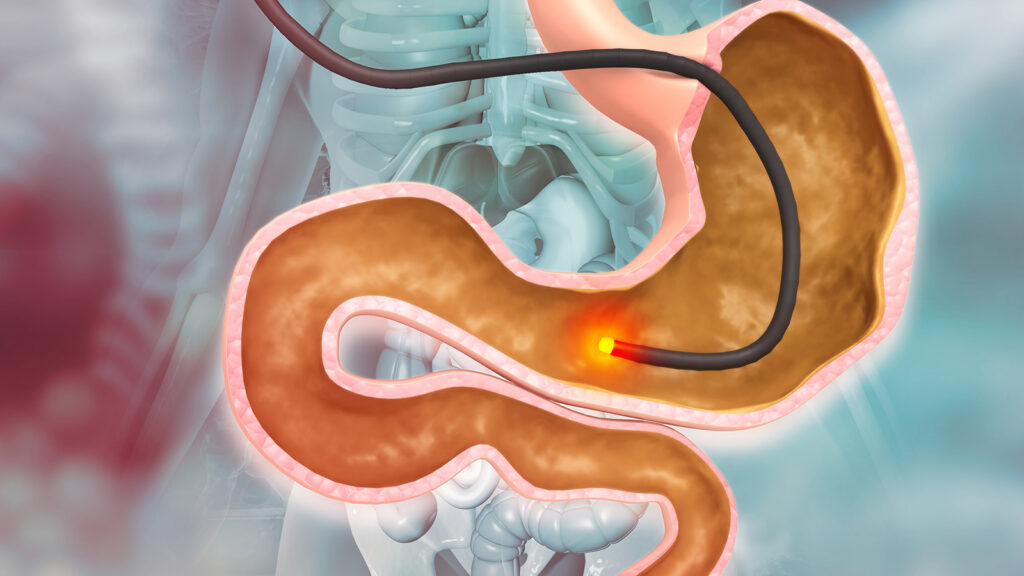

Endoscopy

Endoscopy is a medical procedure that uses a thin, flexible tube with a light and camera (called an endoscope) to look inside the body. It allows doctors to directly view internal organs and tissues, and often take biopsies at the same time.

Colonoscopy

A colonoscopy is a medical procedure that allows doctors to examine the inside of the large intestine (colon and rectum) using a long, flexible tube with a camera and light (a colonoscope).

Uses a thin, flexible tube with a light and camera to examine the inside of organs and cavities.

- Allows direct visualization of tissues

- Can take biopsies during the procedure

- Used for esophagus, stomach, colon, and lungs

Examines the entire colon and rectum using a long, flexible tube with a camera.

- Detects polyps and colorectal cancer

- Can remove polyps during the procedure

- Recommended for routine screening starting at age 45